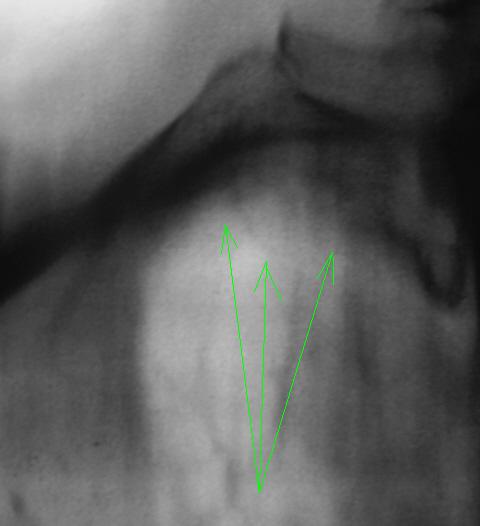

2. А на правой верхушке, помеченное зелеными стрелками - это очаги?

ИзображениеИзображение